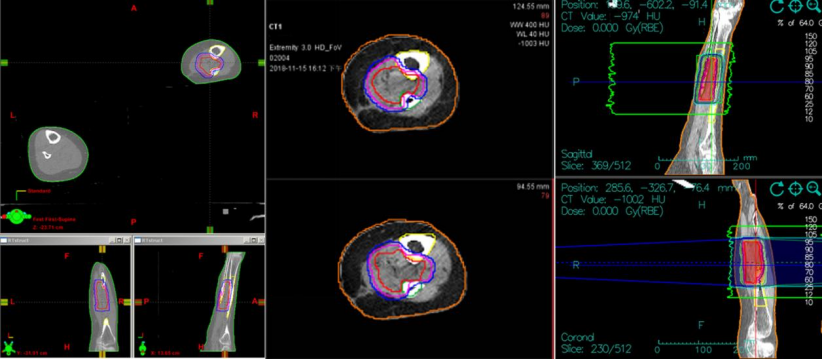

病例二:患者,女,55岁。病史:右小腿脂肪肉瘤,曾于2014年11月17日和2016年3月30日接受两次广泛切除术。第二次术后于2016年5月接受辅助放疗(总剂量50.4Gy/28次,后续加量10Gy/5次)。2018年11月1日,PET-CT和MRI(图1)显示肿瘤复发,病灶位于右胫腓骨中间隙,大小约4.2×2.0 cm。临床诊断为右小腿脂肪肉瘤复发。2018年11月,患者接受重(碳)离子治疗,治疗方案为:总剂量64Gy(RBE),分16次,在28天内完成(每周一至周五,每日一次),照射野设计采用两野计划(水平野和垂直野,见图2)。

图2. 重(碳)离子治疗照射野设计

(示意图为水平野和垂直野的两野照射计划)